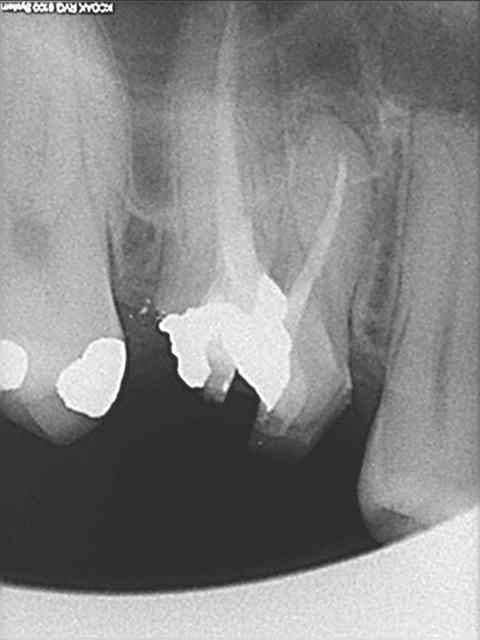

pour votre plaisir mon ami 8 mois d'écarts

fenêtre fermée par du vitalos pas de membrane technique "grosse ouverture"